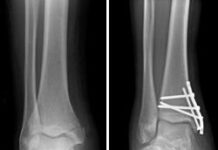

Cómo tratar una Fractura de Tobillo antes de que lleguen los médicos

Una lesión de tobillo no es algo que deba tomarse a la ligera, sino algo que debe tratarse de inmediato, pues podría llegar a...

Clasificación y Tipos de Fracturas

¿Qué es una fractura?

La definición de Fractura es tan sencilla como: la rotura de un hueso. Teniendo en cuenta que puede ser fractura total...